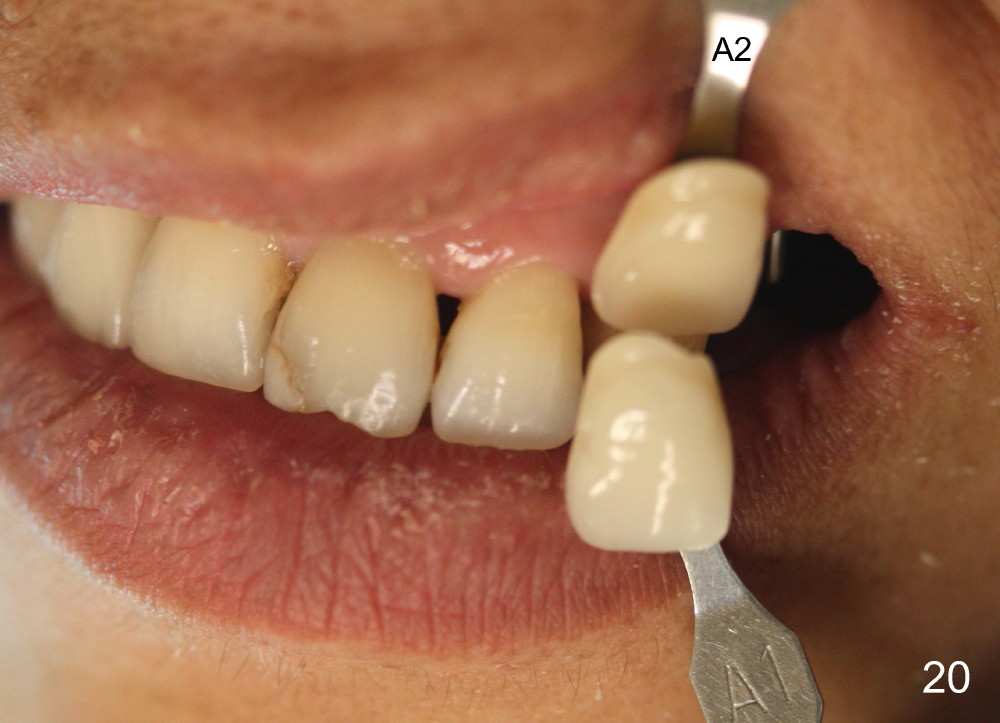

Two PAs are taken 5 months postop (Fig.15,16). Patterns of bone graft (*) between these PAs are different, which suggests presence of the graft buccal to the implant at the site of #14. Another piece of evidence of the graft is that the buccal socket heals (Fig.17 B) without implant thread exposure (Fig.19). These two implants are ready for definitive restoration (Fig.18-20). Fig.21 shows the final restoration 5 months post cementation.